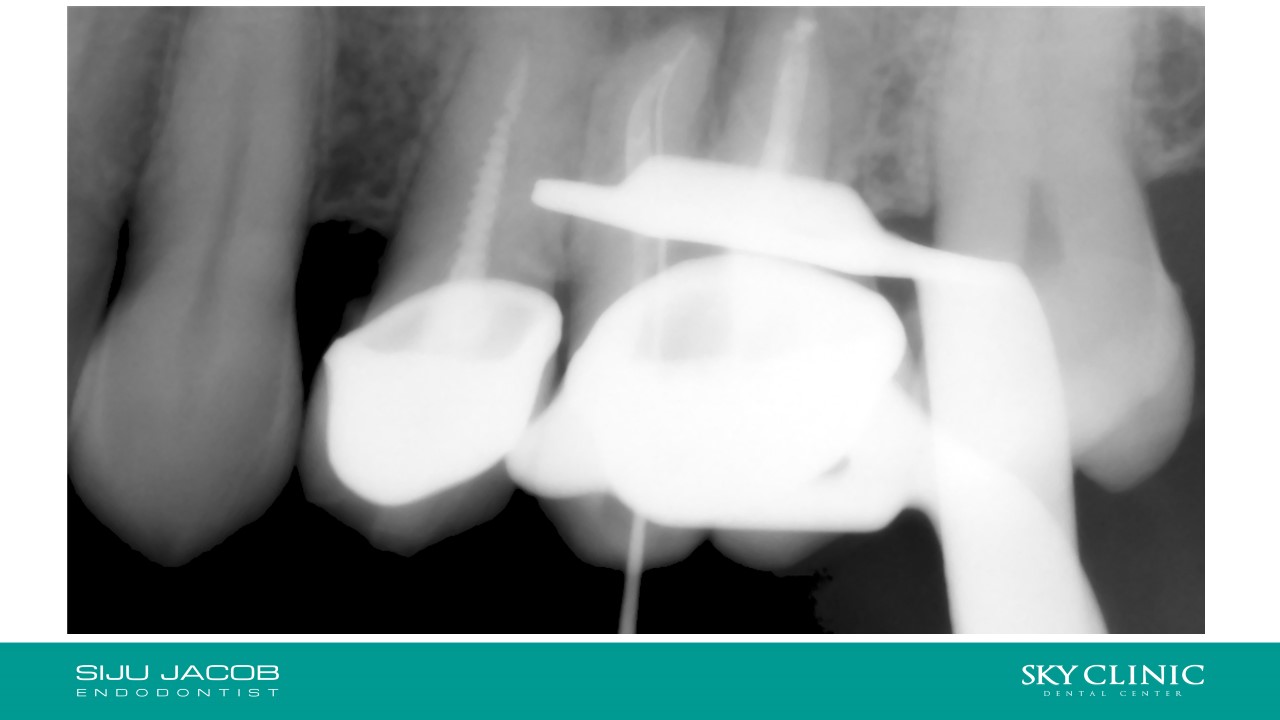

Selective Re-treat of Missed MB2